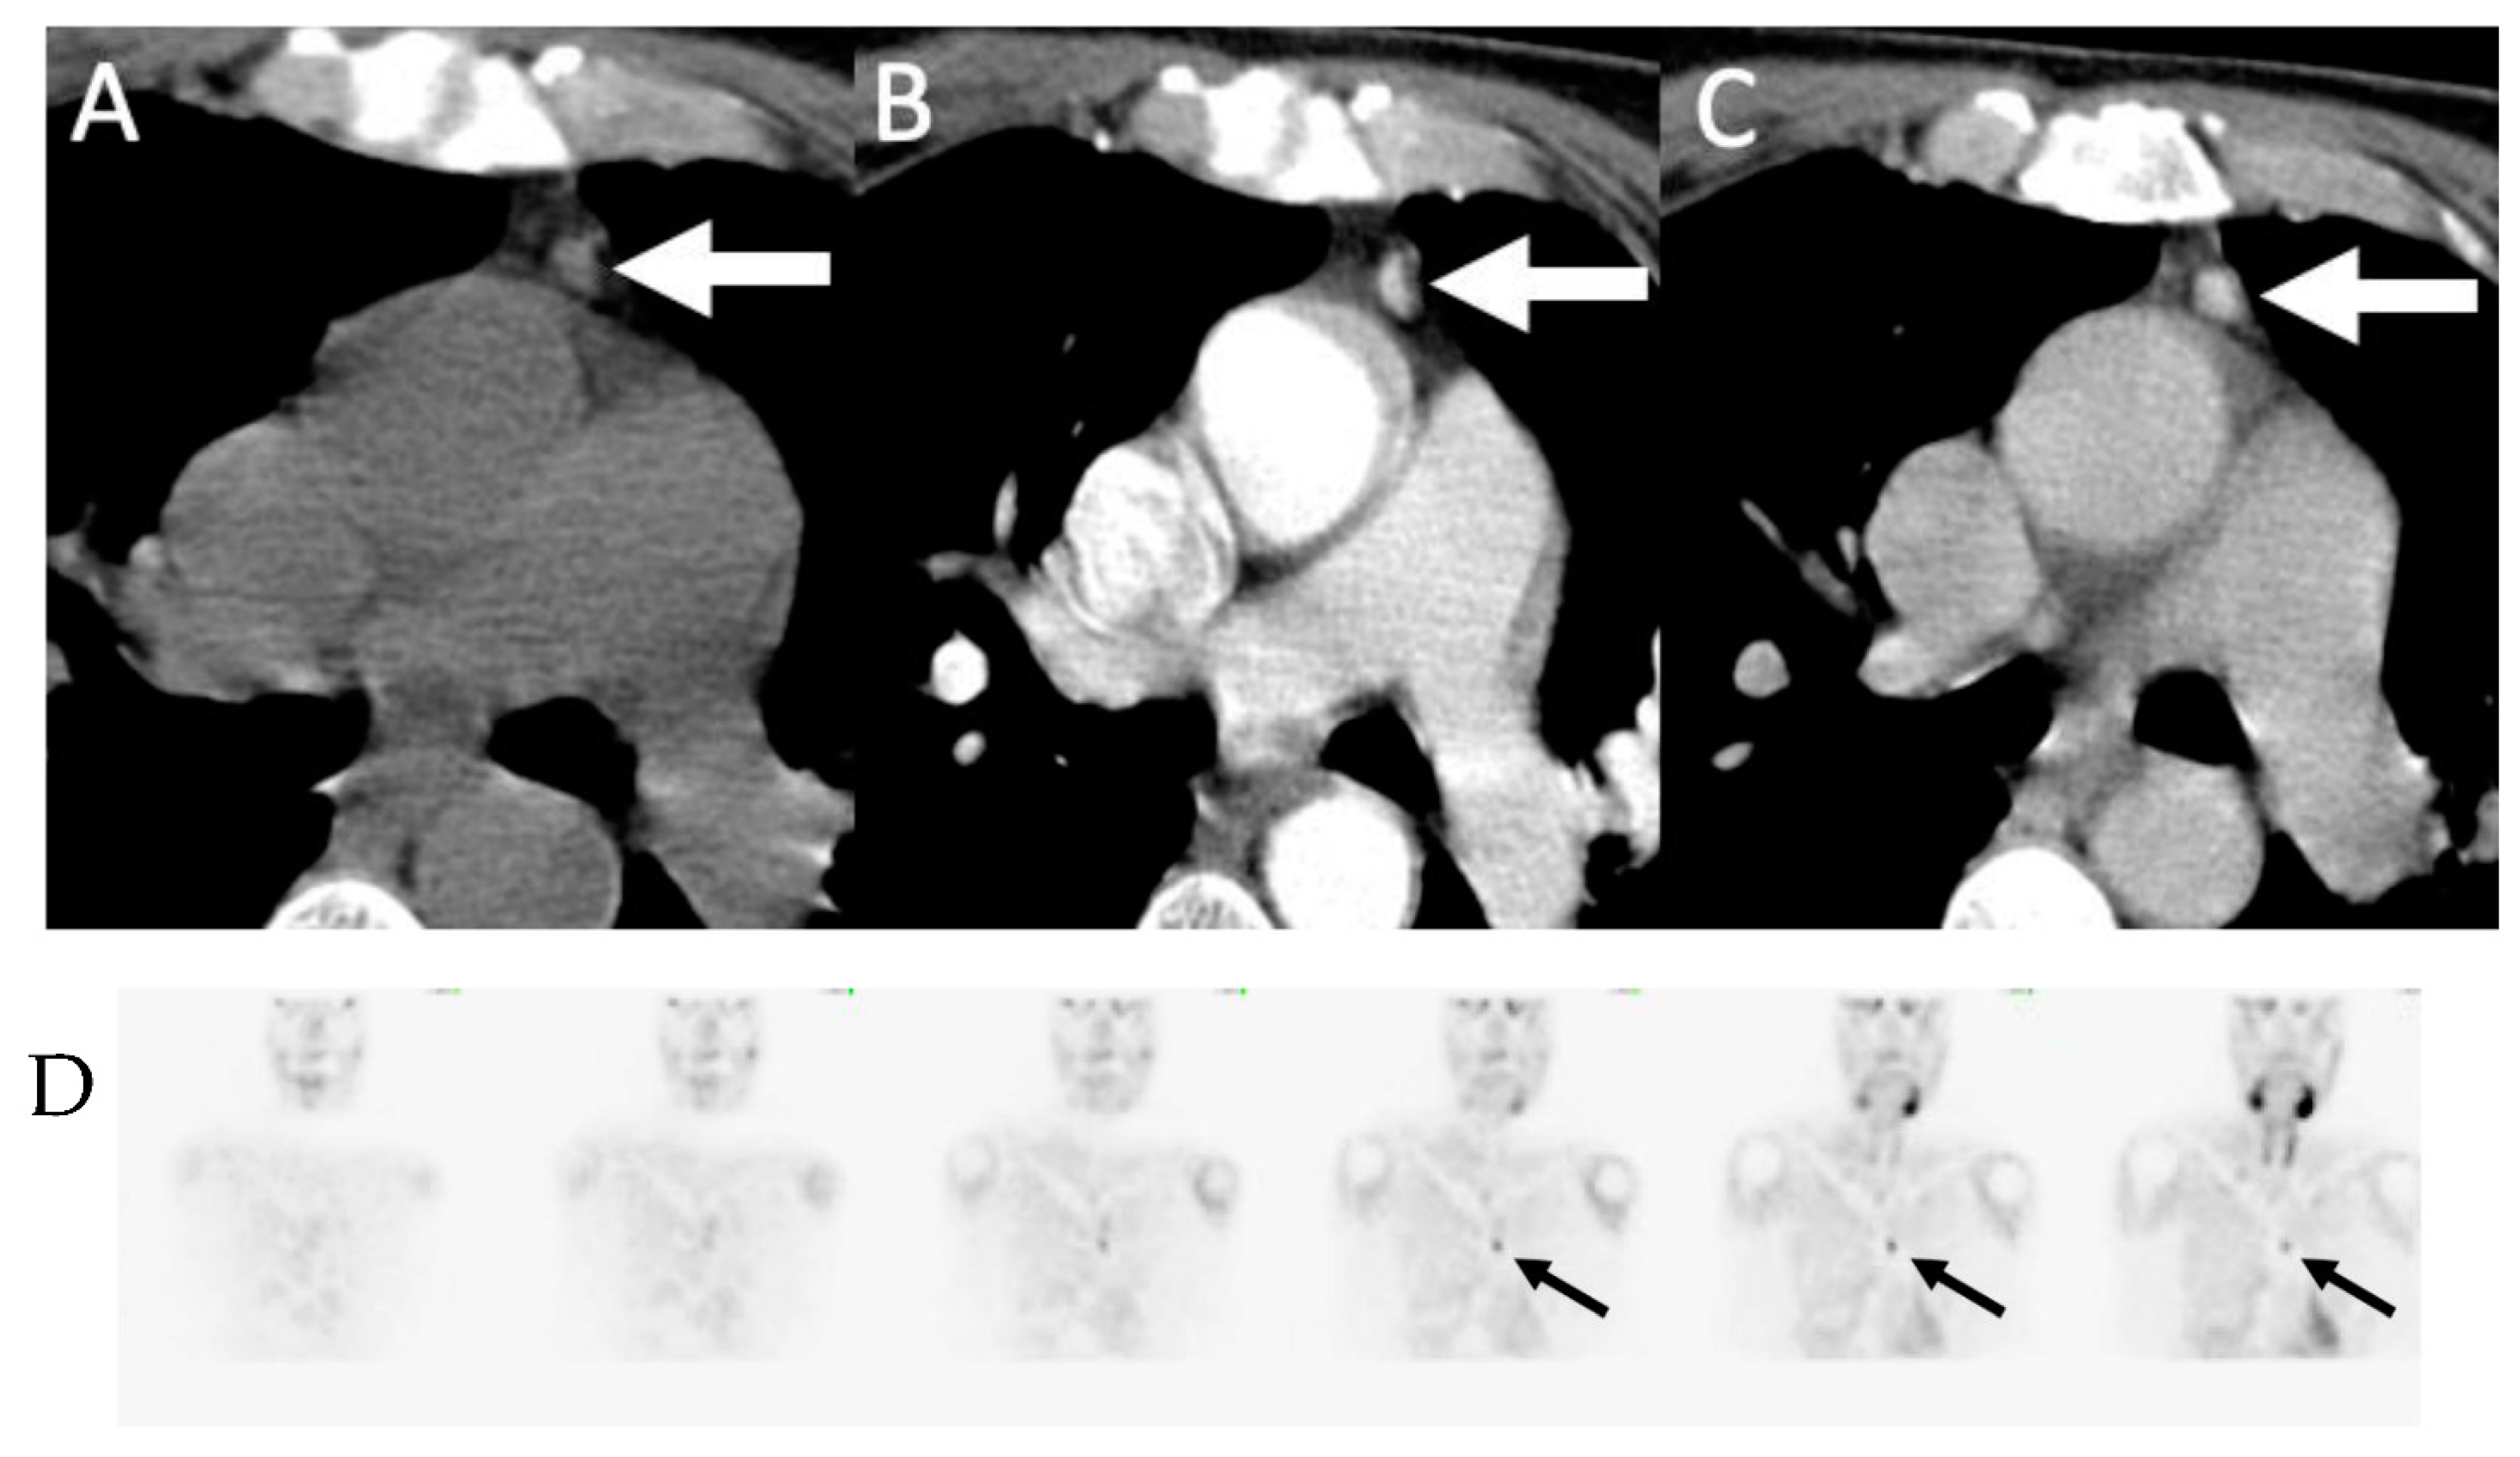

Figure 5.

Ectopic mediastinal adenoma: 62-year-old man with primary hyperparathyroidism 4D-CT demonstrating a small enhancing nodule in the anterior mediastinum (arrows) seen on non-contrast (A), arterial-phase (B) and delayed phase (C) imaging without washout. (D) Coronal early phase sestamibi SPECT images demonstrate mild uptake in the anterior mediastinum, corresponding to the enhancing nodule on 4D-CT. The patient was subsequently taken for thoracoscopic resection which demonstrated an ectopic parathyroid adenoma within thymic tissue.